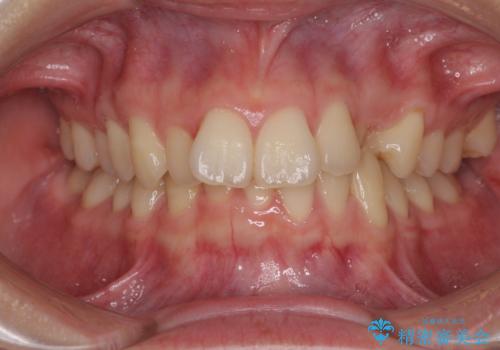

- 咬み合わせが悪いとのことで来院された患者様です。

ぱっと見はインビザラインによる矯正治療も可能と思われましたが、歯根が最も長い犬歯がクロスバイトになっており、インビザラインでは対応困難と判断され、ワイヤー装置にて矯正治療を行うこととしました。